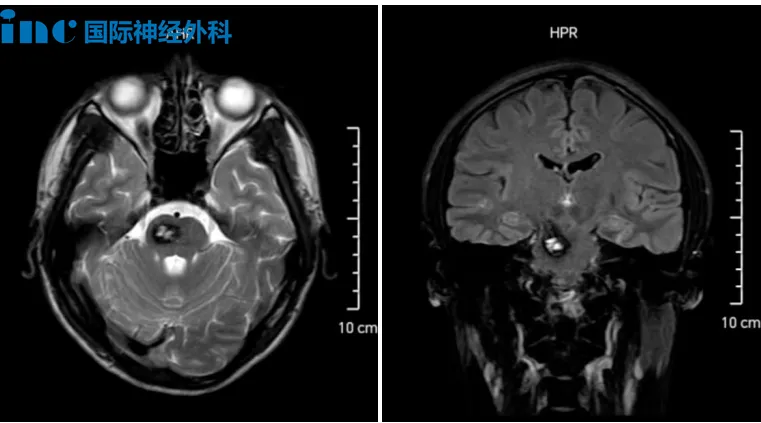

21岁青年面临的手术决策难题

今年9月,21岁男性因头晕症状确诊右侧大脑脚及脑干血管瘤伴出血。多家医院会诊意见存在分歧,部分建议手术但提示面瘫、肢体麻木等风险。当家属得知巴特朗菲教授在华学术交流消息后,立即寻求视频会诊机会。

针对该病例,巴教授分析指出:"血管瘤体积较大,需手术切除干预,否则未来再出血风险较高,可能引发更严重并发症。"他补充说明:"我已完成200余例脑桥部位手术,累计处理373例脑干海绵状血管瘤病例——在该领域我们具备充分技术储备。"